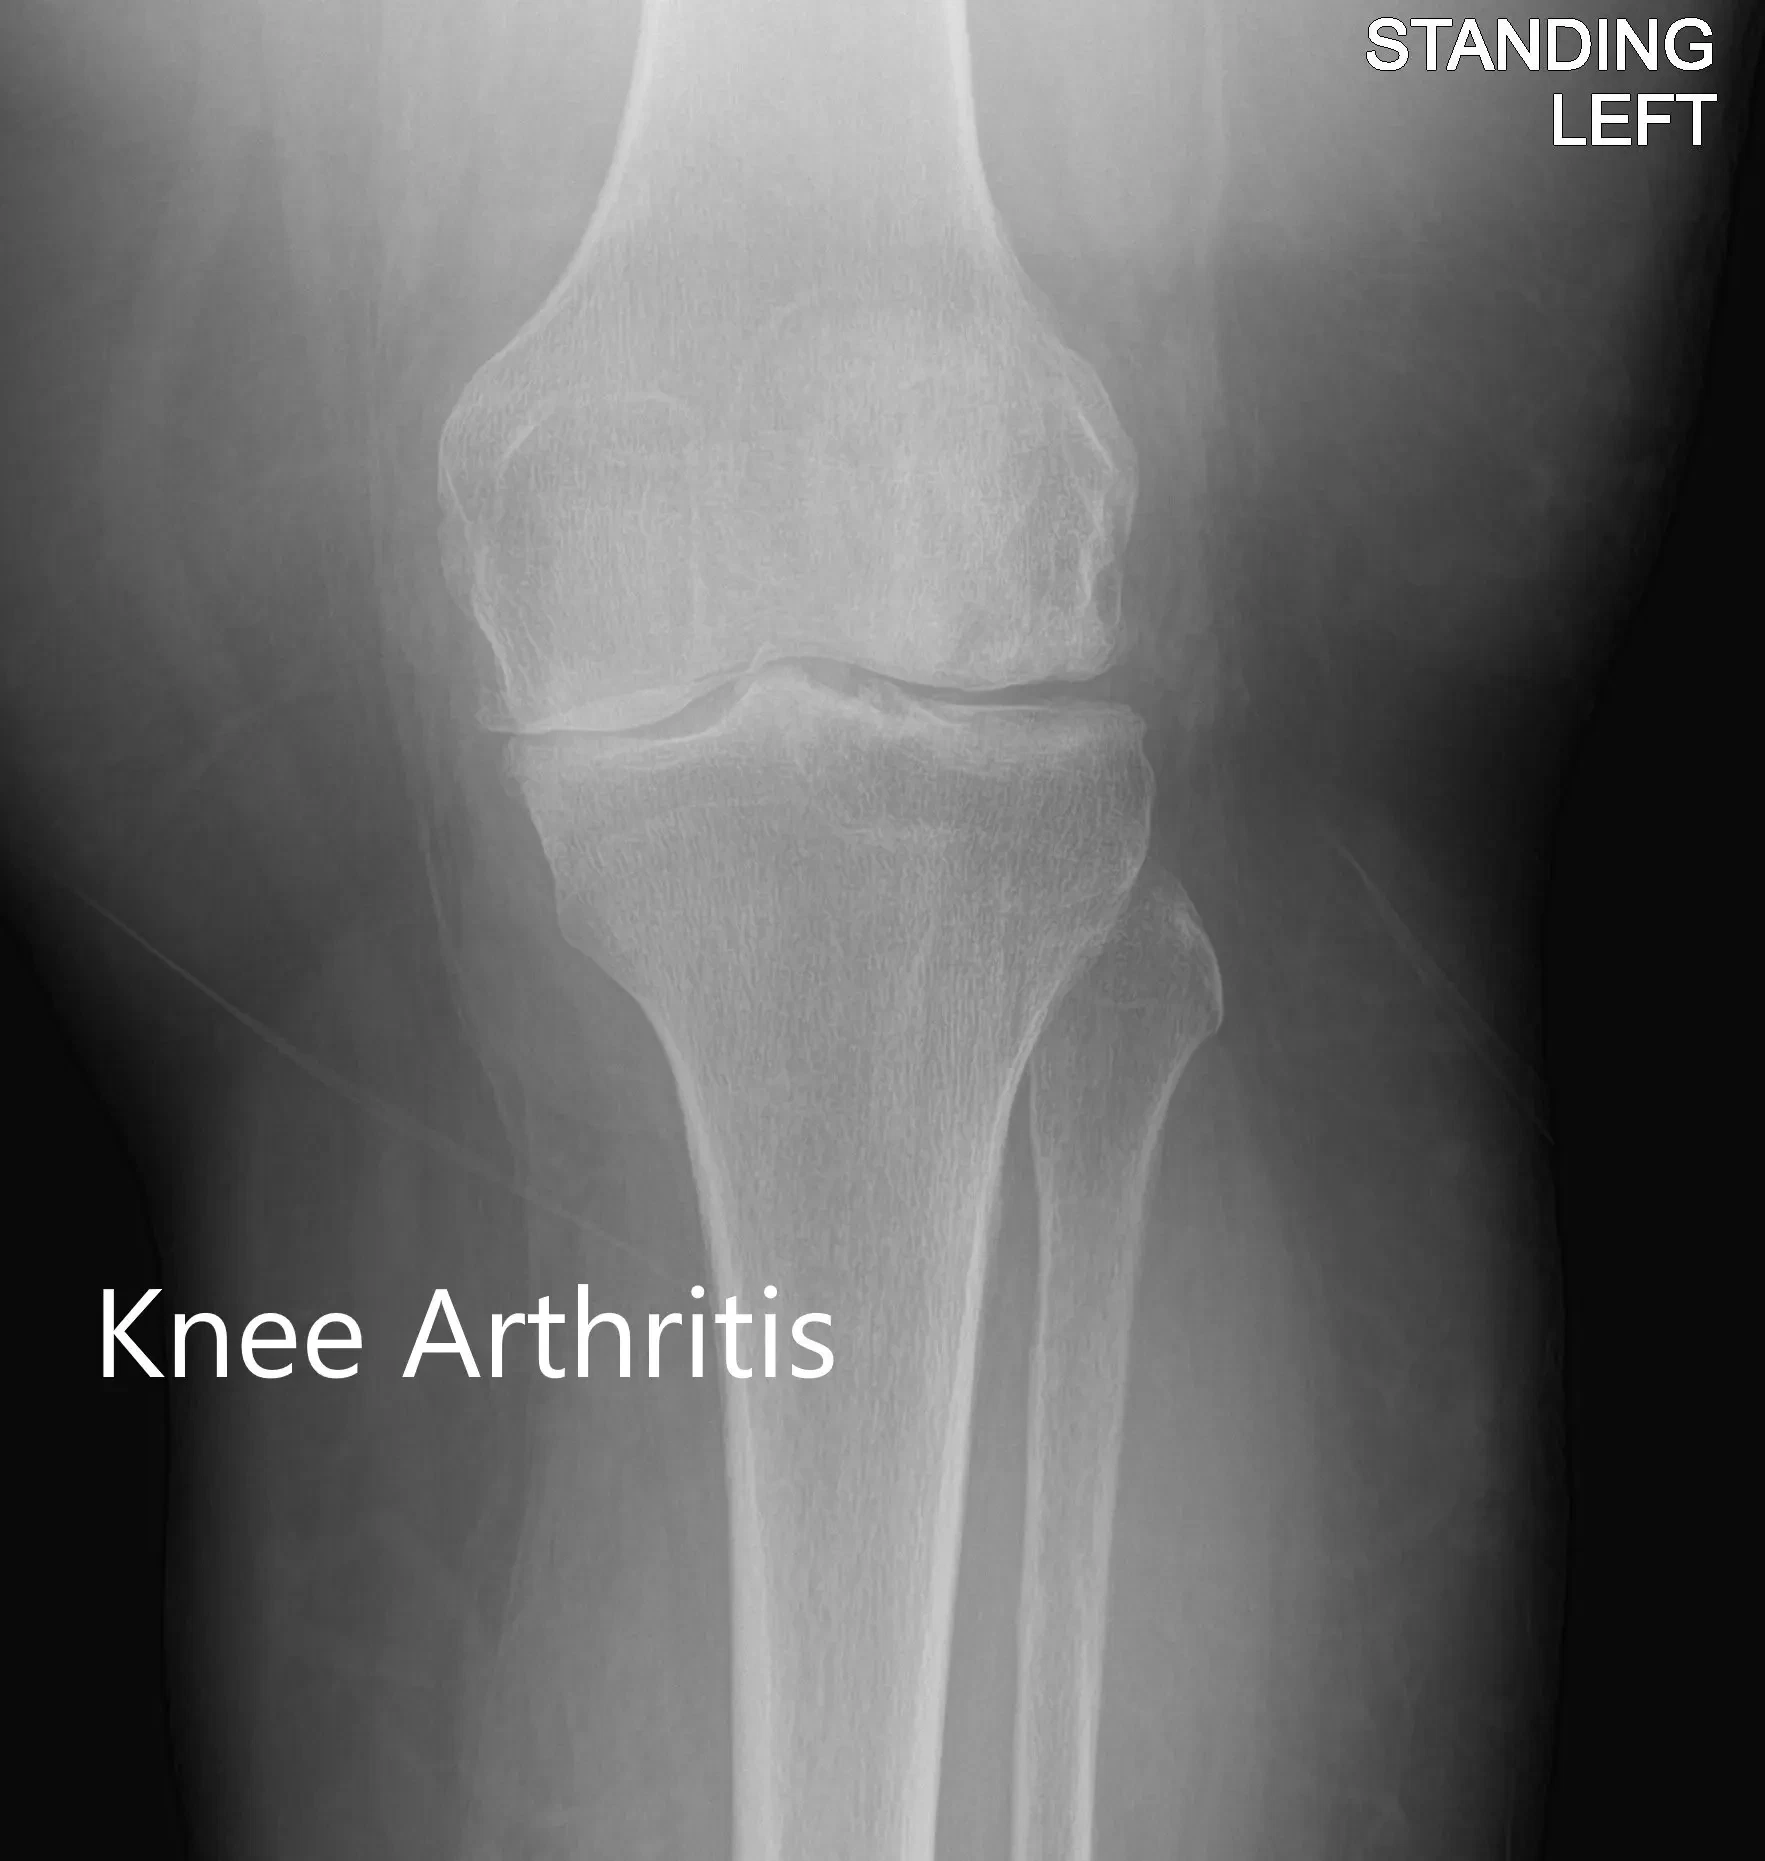

Imaging revealed severe tricompartmental osteoarthritis of the left knee with joint space reduction and osteophytes.

Anteroposterior and lateral view of the left knee